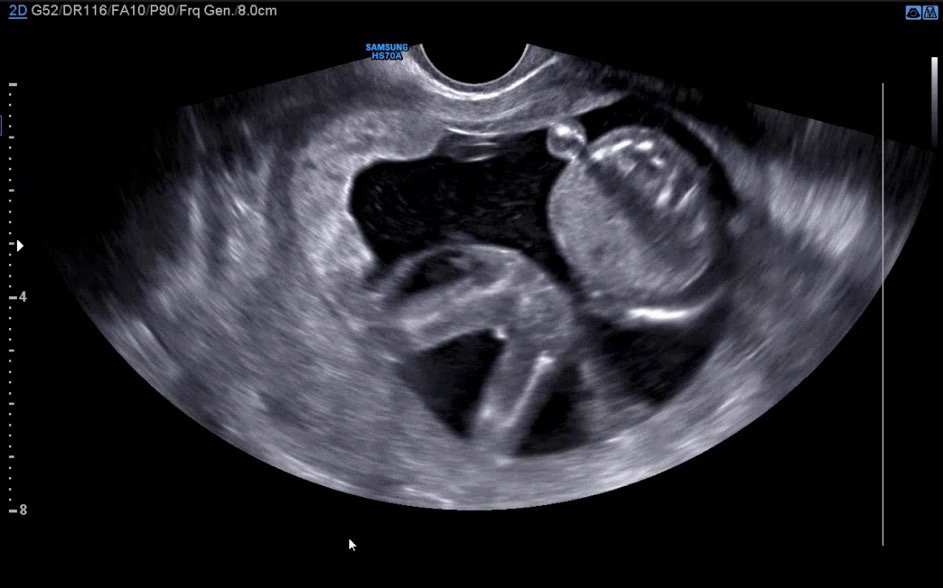

성별좀 봐쥬세요!! 둥이인데 둘째 성별이 너무궁금해용 😂

첫지는 아들이구요!! 둘찌 사진 첨부합니다 15주 0일이에용!!

삼각점이 보이는 것 같아요. 아들에 한표 드립니다.

아들이여